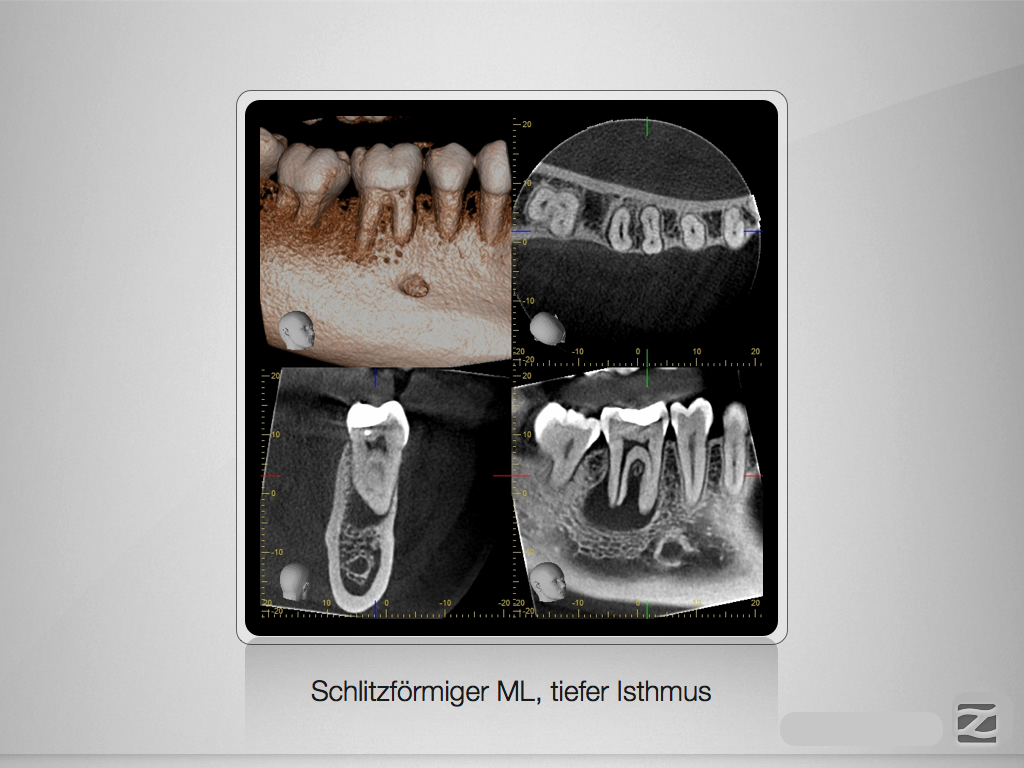

46D.004

Therapieplanung nach DVT